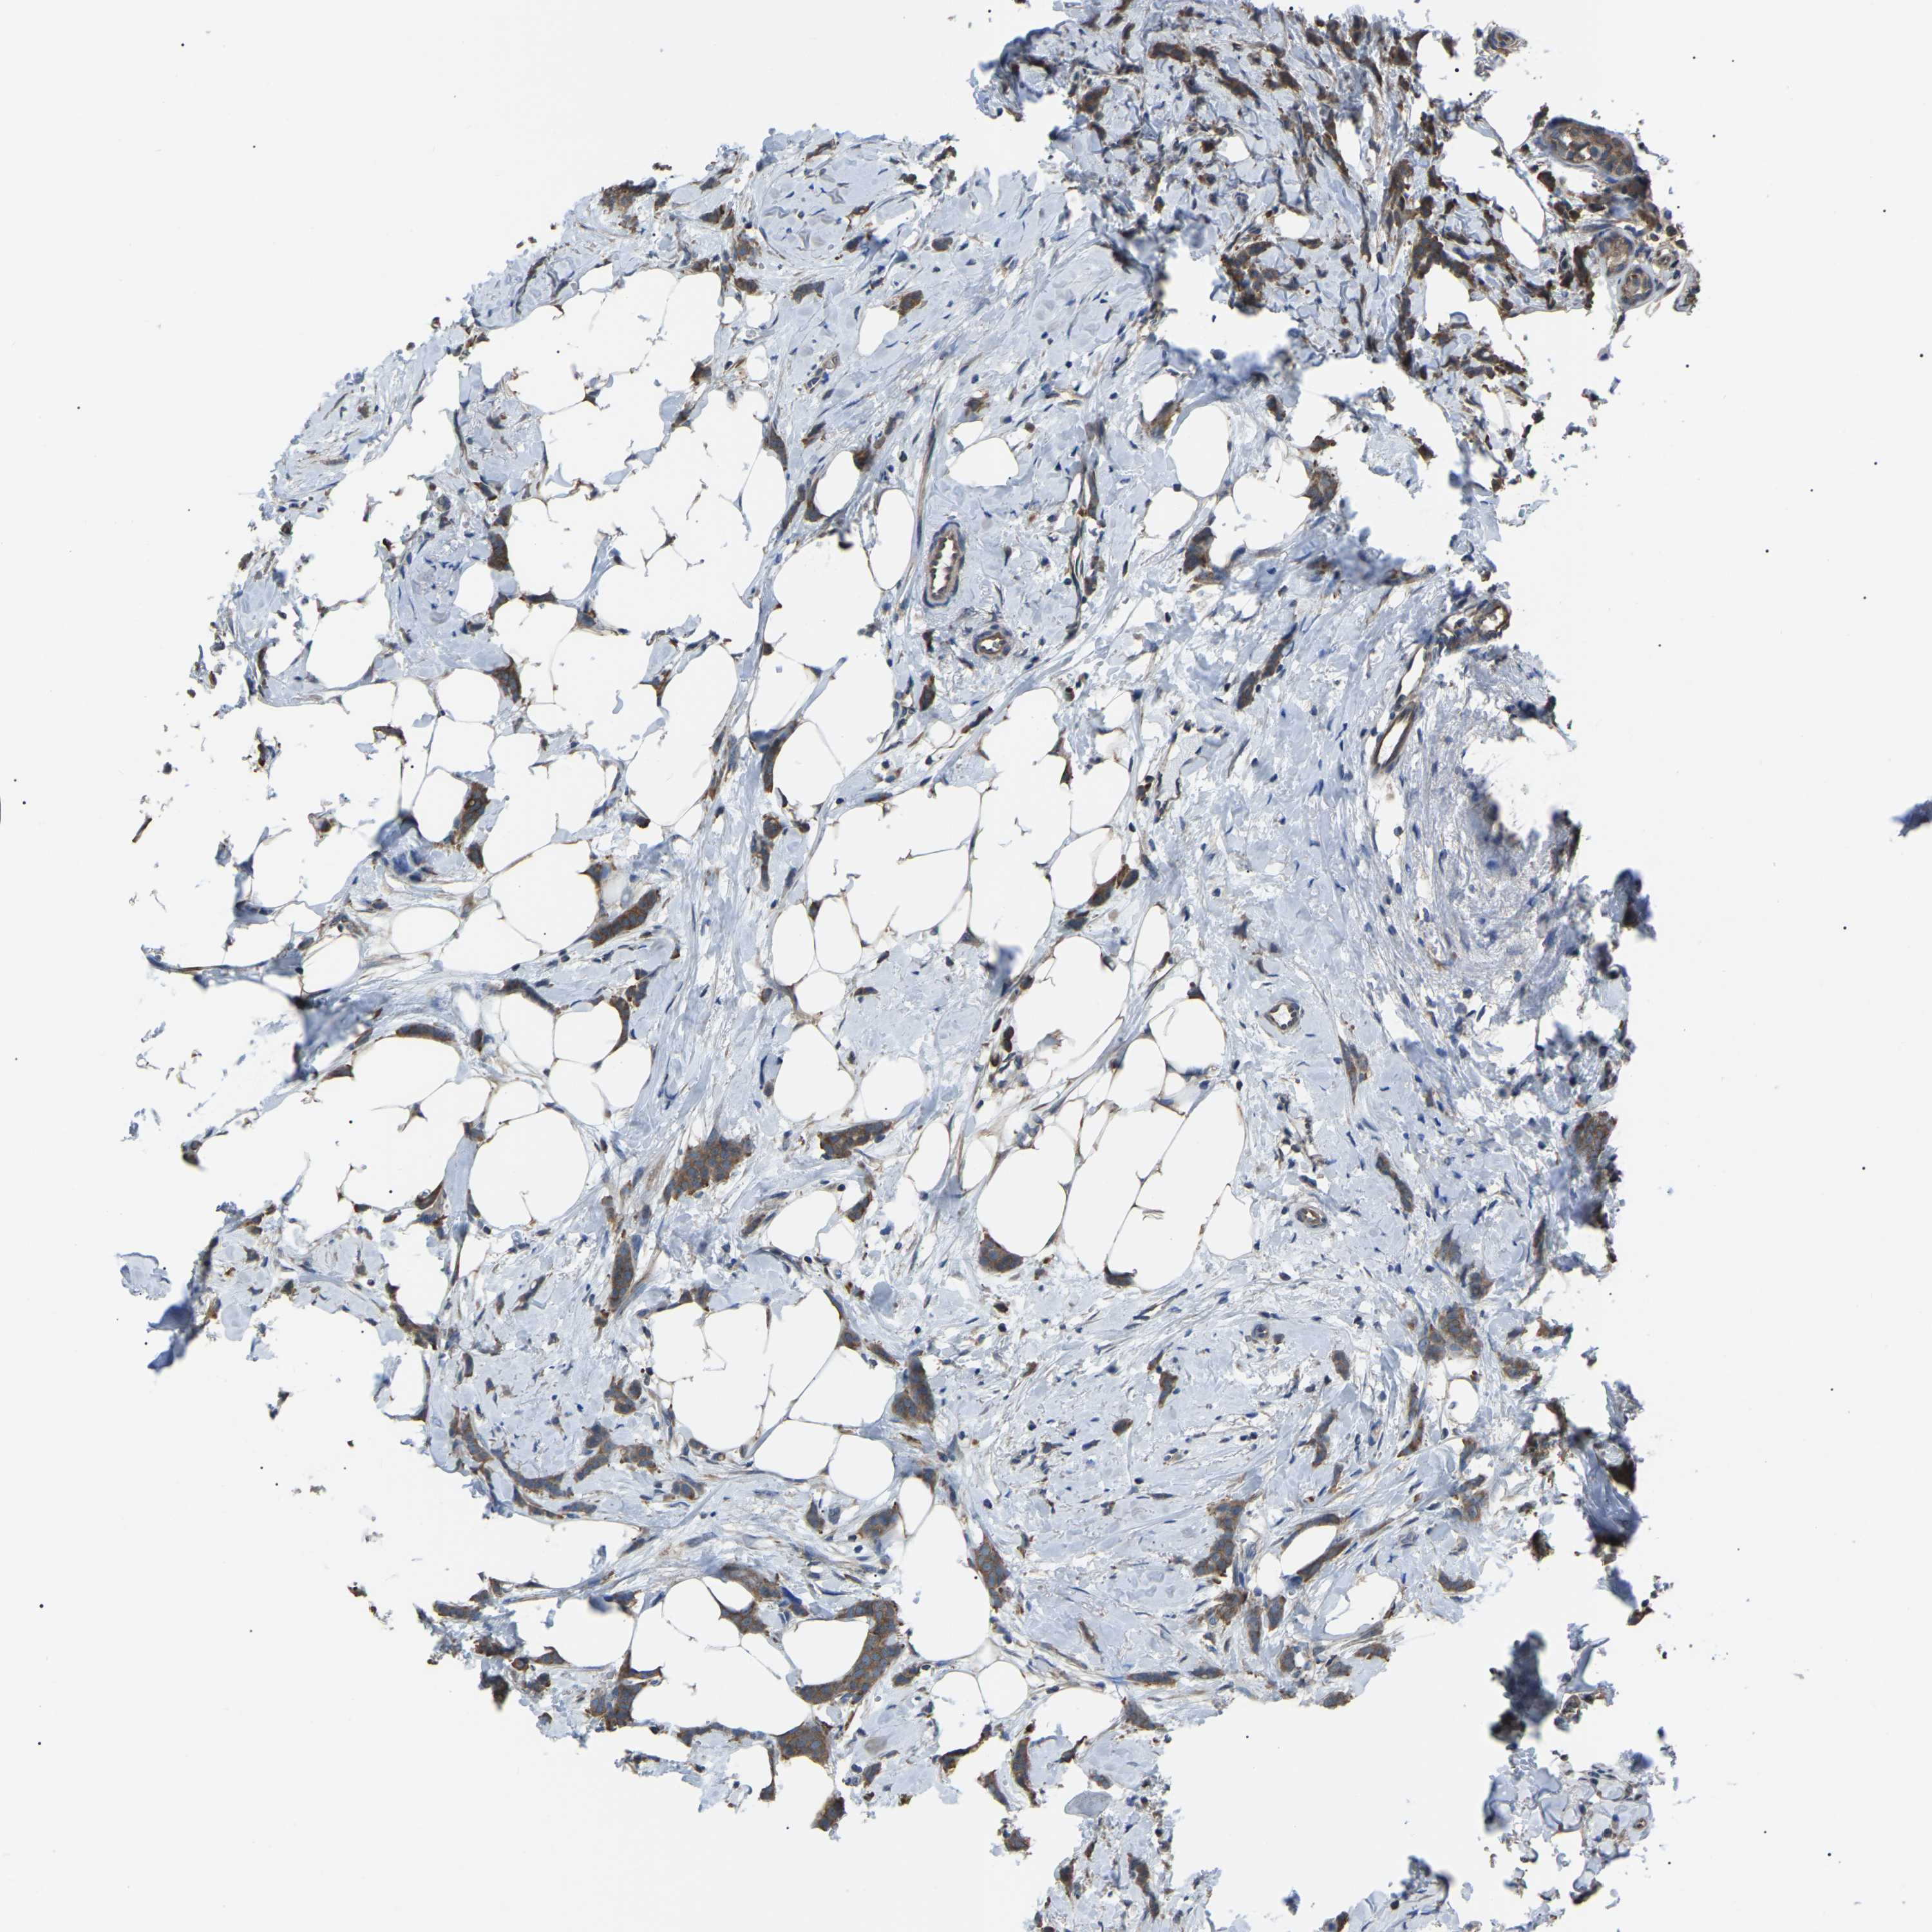

CANCER BREAST CANCER Show tissue menu

BRCA TCGA BRCA VALIDATION PROTEIN EXPRESSION

ANTIBODIES

AND

VALIDATION